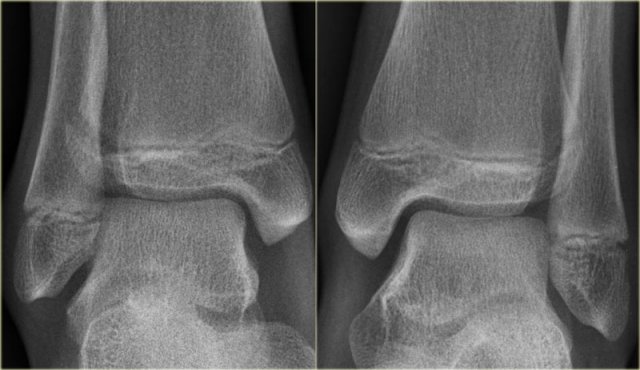

There is a subtle widening of the lateral part of the growth plate of the right ankle.

There is also a very subtle fracture through the epiphysis.

Continue with the CT.

The CT-images show a epiphysiolysis fracture Salter Harris type 3.

This juvenile Tillaux is especially seen in young athletes.

Always look for higher stages of an exorotation injury.